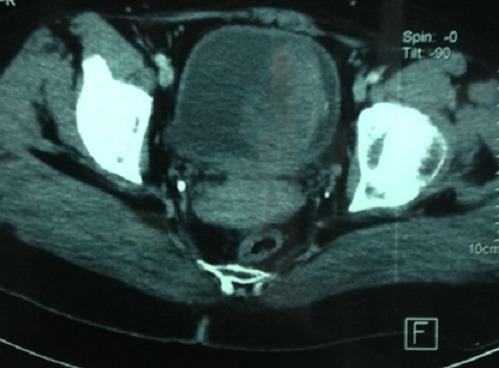

Bladder schwannomas are exceedingly rare, benign or malignant, nerve sheath tumors that are most often discovered in patients with a known diagnosis of Neurofibromatosis type 1 (NF1). A few sporadic case reports of bladder schwannoma have been published in urologic, obstetric/gynecologic, and pathologic journals. We report a case of an isolated schwannoma of the urinary bladder. To our knowledge, this represents only the sixth case of benign schwannoma of the urinary bladder in a patient without von Recklinghausen disease.

膀胱神经鞘瘤极为罕见,是一种良性或恶性的神经鞘肿瘤,最常出现在已确诊为1型神经纤维瘤病(NF1)的患者中。泌尿外科、妇产科和病理学杂志上已发表了几例膀胱神经鞘瘤的散发病例报告。我们报告一例孤立性膀胱神经鞘瘤病例。据我们所知,这是仅有的第六例在无冯雷克林霍增氏病患者中发生的膀胱良性神经鞘瘤病例。